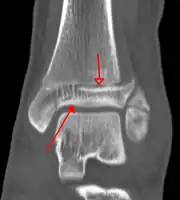

On X-rays, there can be a fracture of the medial malleolus, the lateral malleolus, or of the anterior/posterior margin of the distal tibia. [17] If both the lateral and medial malleoli are broken, this is called a bimalleolar fracture[18]. If the posterior malleolus is also fractured, this is called a trimalleolar fracture. [19]

A triplane fracture of the ankle as seen on CT